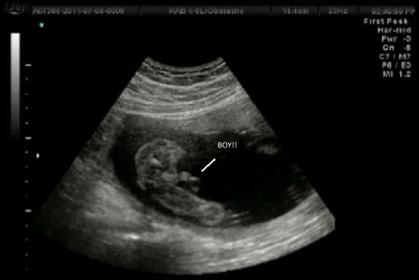

And for good measure, here is the "potty shot" from DS at 19w6d:

Attachment 16691